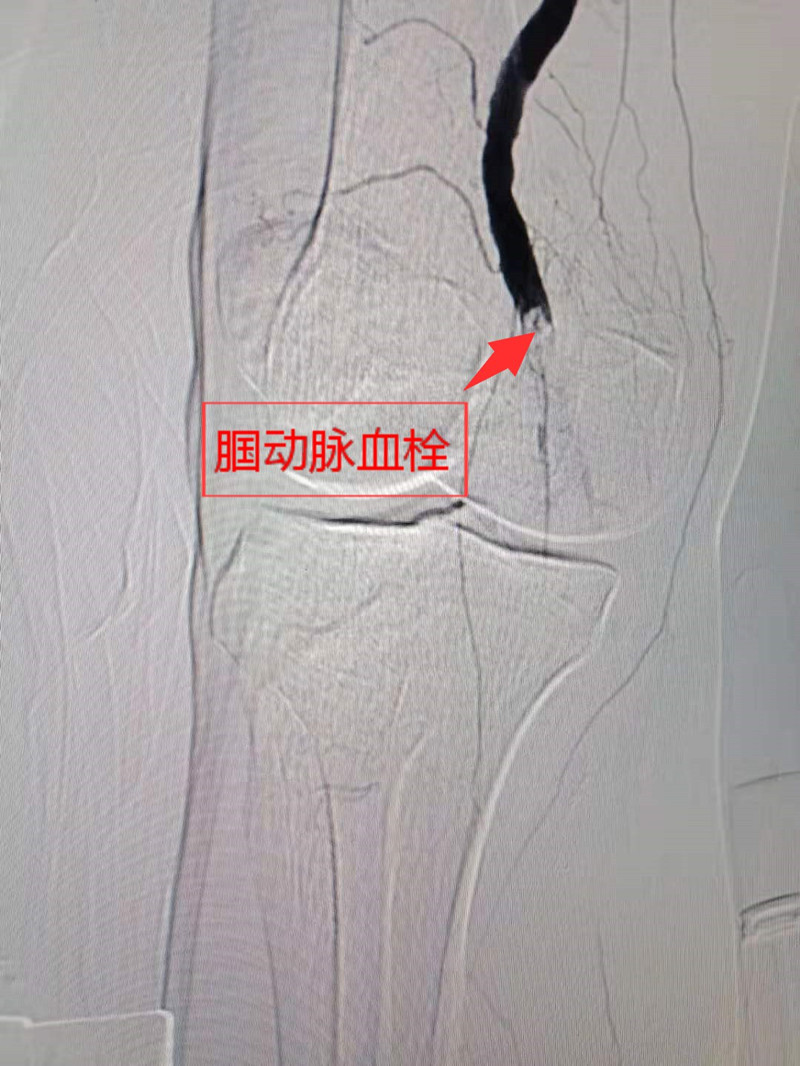

患者袁某某,男性,88岁。12月初开始,患者自觉行走后下肢疼痛,逐渐感觉丧失、麻痹,一直未给予任何治疗。上述症状逐渐加重,患者行走距离变短,右下肢疼痛加重。因其儿子在外地打工,其去看望,遂就诊于浙江大学附属第一医院,查下肢CTA示:双侧腘动脉远端动脉未见造影剂充盈,腘动脉血栓形成考虑;双下肢动脉硬化;左肾动脉血栓形成考虑。右下肢静脉彩超示:1.右下肢腘动脉血栓形成,右下肢动脉硬化伴斑块形成;2.右下肢深静脉血流通畅,建议行介入治疗。

而后患者家属听说我院外周介入科可行该种介入治疗手术,遂于第二日由外地返至我院就诊。拟"右下肢动脉栓塞"收住我院外周介入科。完善相关辅助检查后,我科给予该患者行“右股动脉、腘动脉、腓动脉造影+右股动脉切开取栓术”。术后患者右下肢皮温恢复,右侧足背动脉搏动可触及。